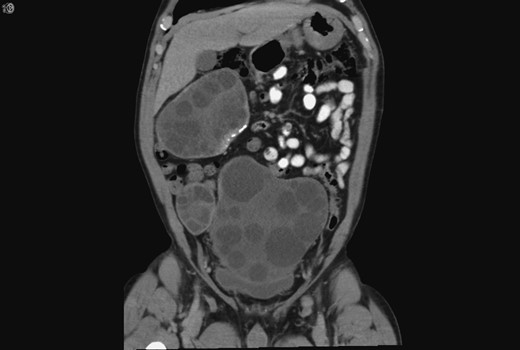

A 59-year-old Bosnian male presented with abdominal discomfort. A 20 × 10 cm2 suprapubic mass was palpable. An abdominal ultrasound scan (US) revealed a large complex pelvic mass, subsequent abdominal and pelvic computed tomography (CT) revealed multiple complex peritoneal cysts suggestive of hydatid disease (Fig. 1).

Coronal CT showing the hydatid cysts with daughter cysts within the larger structures.